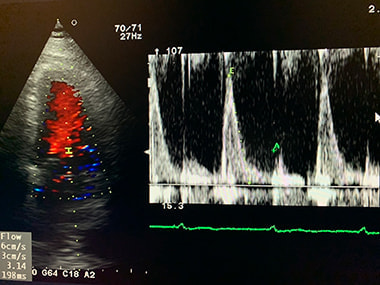

心エコー検査:

心臓が正常に働いているかどうかを調べる検査です。心臓の大きさ、動き、

弁の状態、血液の流れなどを調べ、弁膜症、心筋症、心不全などを診断します。

心臓